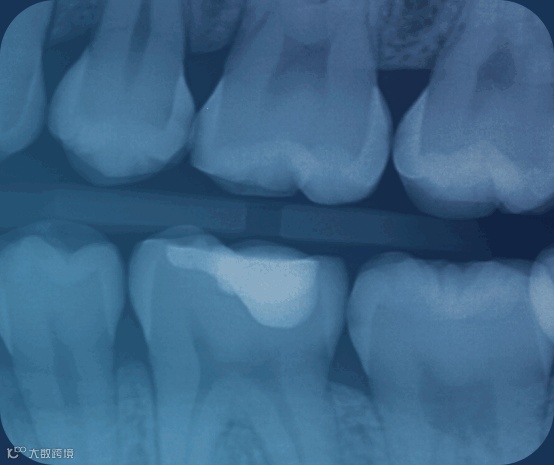

Pearl公司的Second Opinion软件是一个实时的牙科人工智能平台,可以自动检测牙科X光片中的多种病症,给牙医提供第二视角,从而提高放射学诊断的准确性。

Second Opinion是业内第一个也是唯一一个获得美国食品药品监督管理局(FDA)许可的椅旁人工智能软件,利用计算机视觉技术,帮助牙医在牙科X光片中发现多种疾病和其他情况,可以识别包括龋齿、牙石和根尖脓肿等在内的多种常见牙科病症。

Pearl的人工智能可以实时地将检测结果显示在患者面前的屏幕上,帮助牙医提高X光片评估的准确性,并更好地向患者解释诊断结果。通过这种集成,VisiQuick软件的用户可以直接在软件中使用Second Opinion对2D口腔X光图像进行人工智能评估。